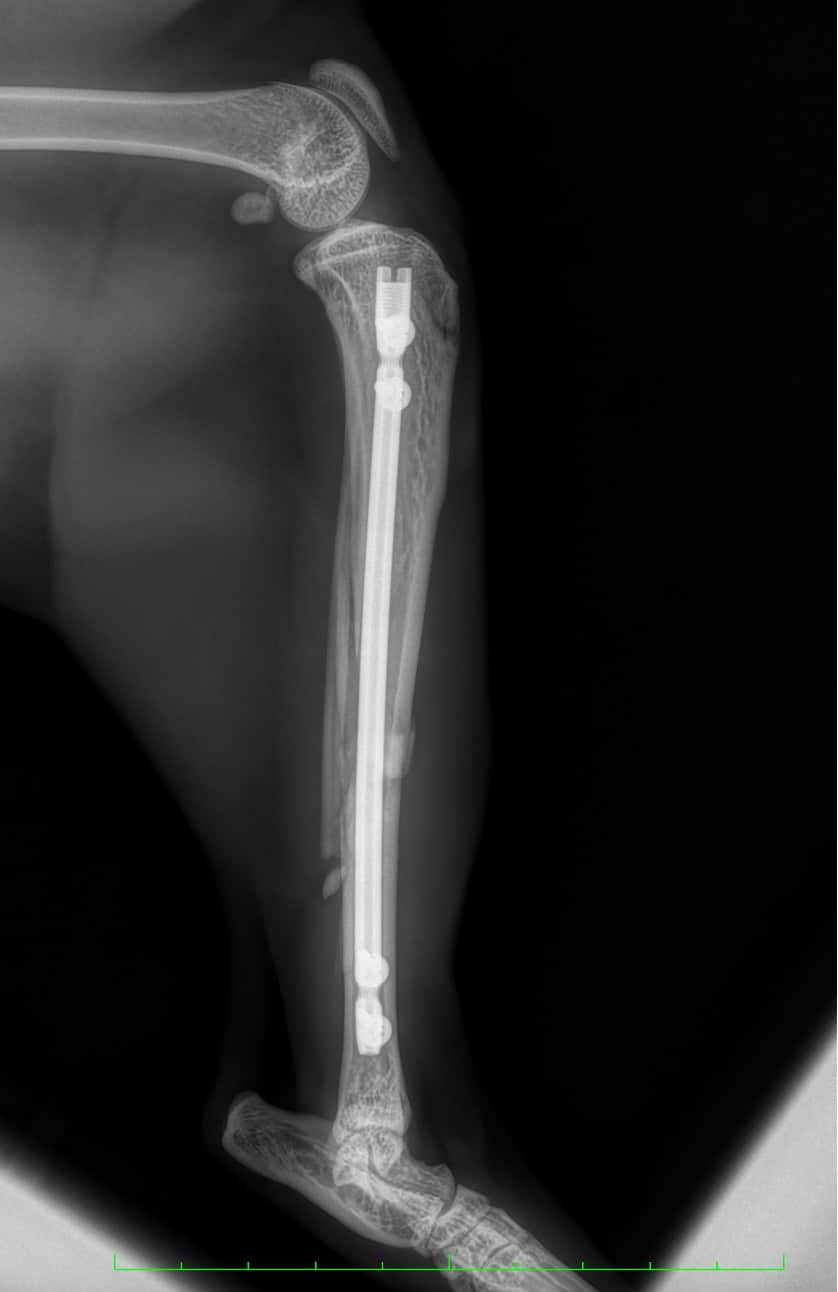

Les fractures chez le chat